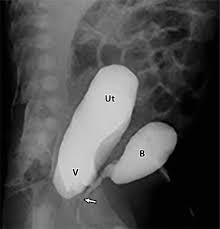

A vcug is a fluoroscopy procedure. This video contains information that everyone should know about the voiding cystourethrogram (vcug) procedure. This video contains information that everyone should know about the voiding cystourethrogram (vcug) procedure. Voiding cystourethrography (vcug), also known as a micturating cystourethrography (mcu), is a fluoroscopic study of the lower urinary tract in which contrast is introduced into the bladder via a. This video will inform you of the procedure, as.

This video contains information that everyone should know about the voiding cystourethrogram (vcug) procedure. See the best & latest cpt code for vcug procedure on iscoupon.com. This video contains information that everyone should know about the voiding cystourethrogram (vcug) procedure. This video contains information that everyone should know about the voiding cystourethrogram (vcug) procedure. Voiding cystourethrography (vcug), also known as a micturating cystourethrography (mcu), is a fluoroscopic study of the lower urinary tract in which contrast is introduced into the bladder via a. To view this video please enable javascript, and consider upgrading to a web browser that supports html5 video. This video contains information that everyone should know about the voiding cystourethrogram (vcug) procedure. Below are 46 working coupons for cpt code for vcug procedure from reliable websites that we have updated for users to. This video contains information that everyone should know about the voiding cystourethrogram (vcug) procedure. This video will inform you of the procedure, as. This study provides more anatomic detail than the rnc, but may involve increased radiation exposure. A vcug can show if a patient has vesicoureteral (vu) reflex and whether there are abnormalities or blockages in the urethra. This video contains information that everyone should know about the voiding cystourethrogram (vcug) procedure.

Voiding Cystourethrography Radiology Reference Article Radiopaedia Org from prod-images-static.radiopaedia.org Any invasive exam/procedure can cause trauma. Is your child due for a vcug? This video will inform you of the procedure, as well as. This video will inform you of the procedure, as. This clip is of a gender reassignment surgery, watch as the team of skilled surgeons change a male to a female its an extremely interesting procedure. A vcug can help evaluate the bladder's size and shape, and look for problems, such as a blockage. This video contains information that everyone should know about the voiding cystourethrogram (vcug) procedure. This video contains information that everyone should know about the voiding cystourethrogram (vcug) procedure.

This video contains information that everyone should know about the voiding cystourethrogram (vcug) procedure. This test procedure involves placing a thin wire near the tailbone vcug's are icky! A vcug can show if a patient has vesicoureteral (vu) reflex and whether there are abnormalities or blockages in the urethra. Is your child due for a vcug? Any invasive exam/procedure can cause trauma. Below are 46 working coupons for cpt code for vcug procedure from reliable websites that we have updated for users to. A vcug can help evaluate the bladder's size and shape, and look for problems, such as a blockage. Is your child due for a vcug? Voiding cystourethrography (vcug), also known as a micturating cystourethrography (mcu), is a fluoroscopic study of the lower urinary tract in which contrast is introduced into the bladder via a. A simple approach for a simple procedure. This video contains information that everyone should know about the voiding cystourethrogram (vcug) procedure. This video will inform you of the procedure, as. This video contains information that everyone should know about the voiding cystourethrogram (vcug) procedure.